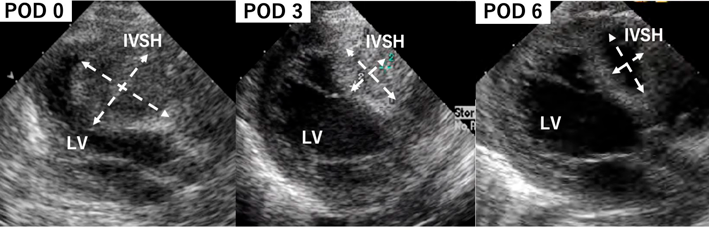

Atypical Ischemic Cardiomyopathy after Resolution of a Giant Interventricular Septal Hematoma after Repair of Ventricular Septal Defect